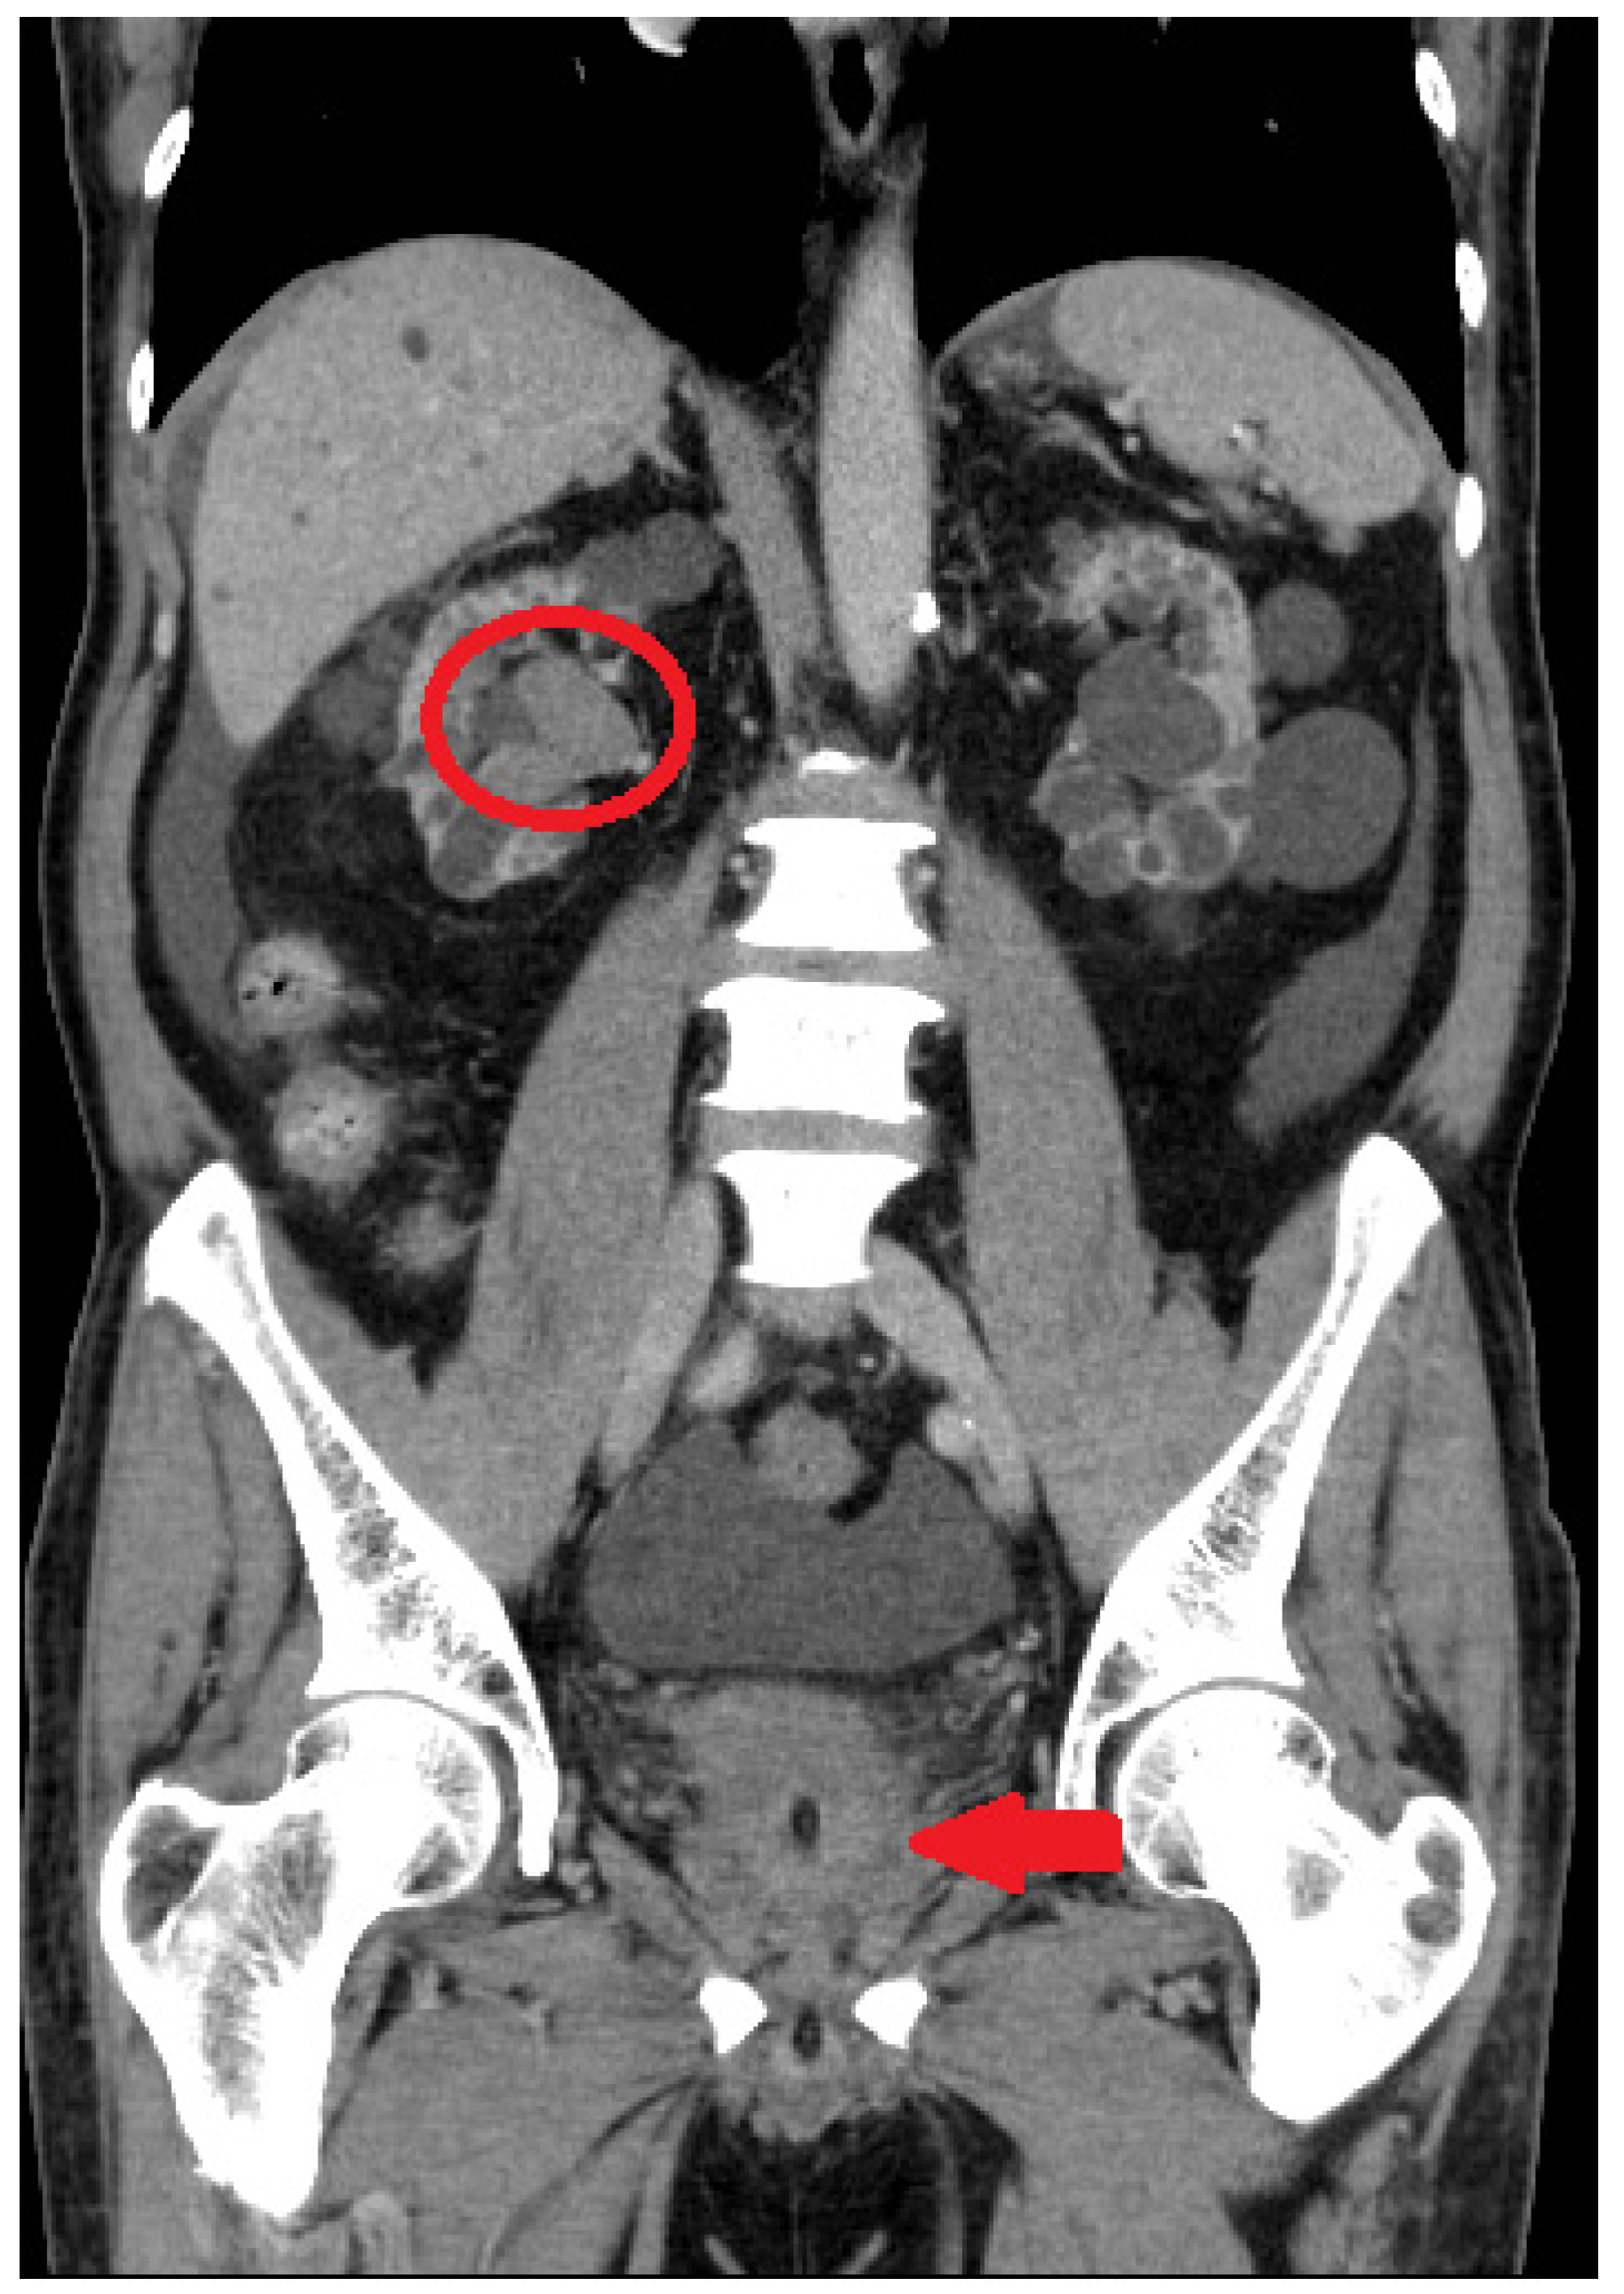

2.1. Initial Assessment

2.2. Robot-Assisted CUTE